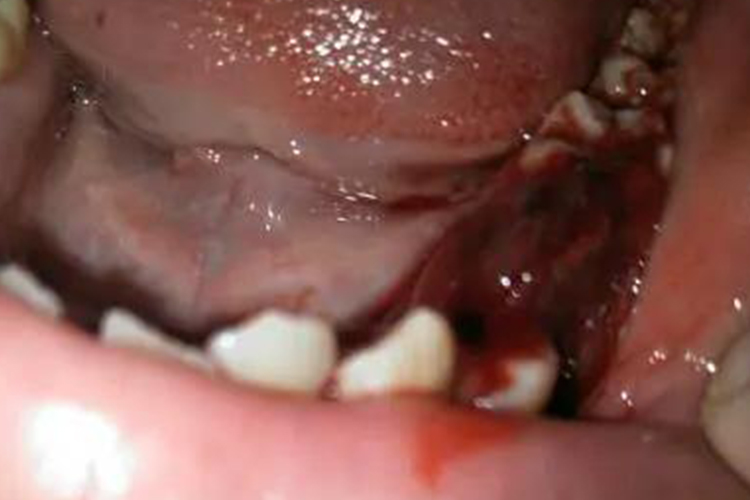

出血倾向是本病的突出表现,以皮肤黏膜为主,可见患者牙龈出血等,外伤或小手术(如拔牙)后的出血也较常见;出血可随年龄增长而减轻。